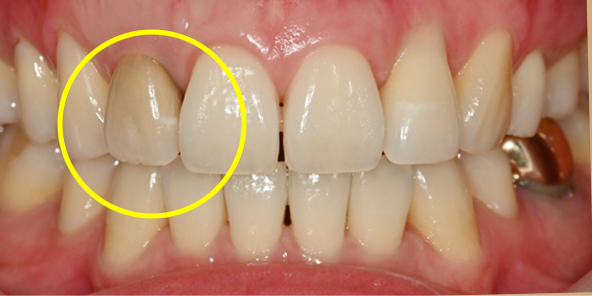

Final Implant Results

BEFORE/AFTER

AFTER